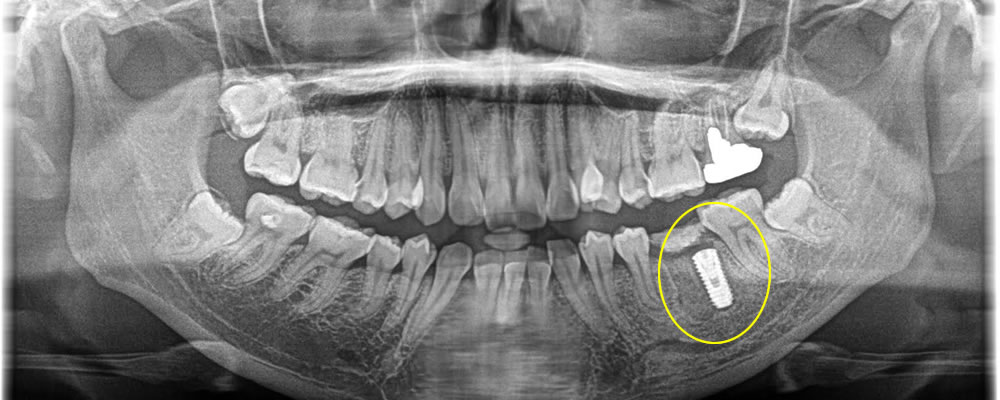

4ヵ月後に2次オペを行い、完全閉鎖をしている歯茎よりインプラント体の頭を出して骨とインプラント体がオステオインテグレーション(結合)している事を確認しました。

その後、型取りを2度行って上部に歯を作成しました。骨の退縮も最小限に抑える事ができ、綺麗な歯を作成する事ができ満足して頂く事ができました。